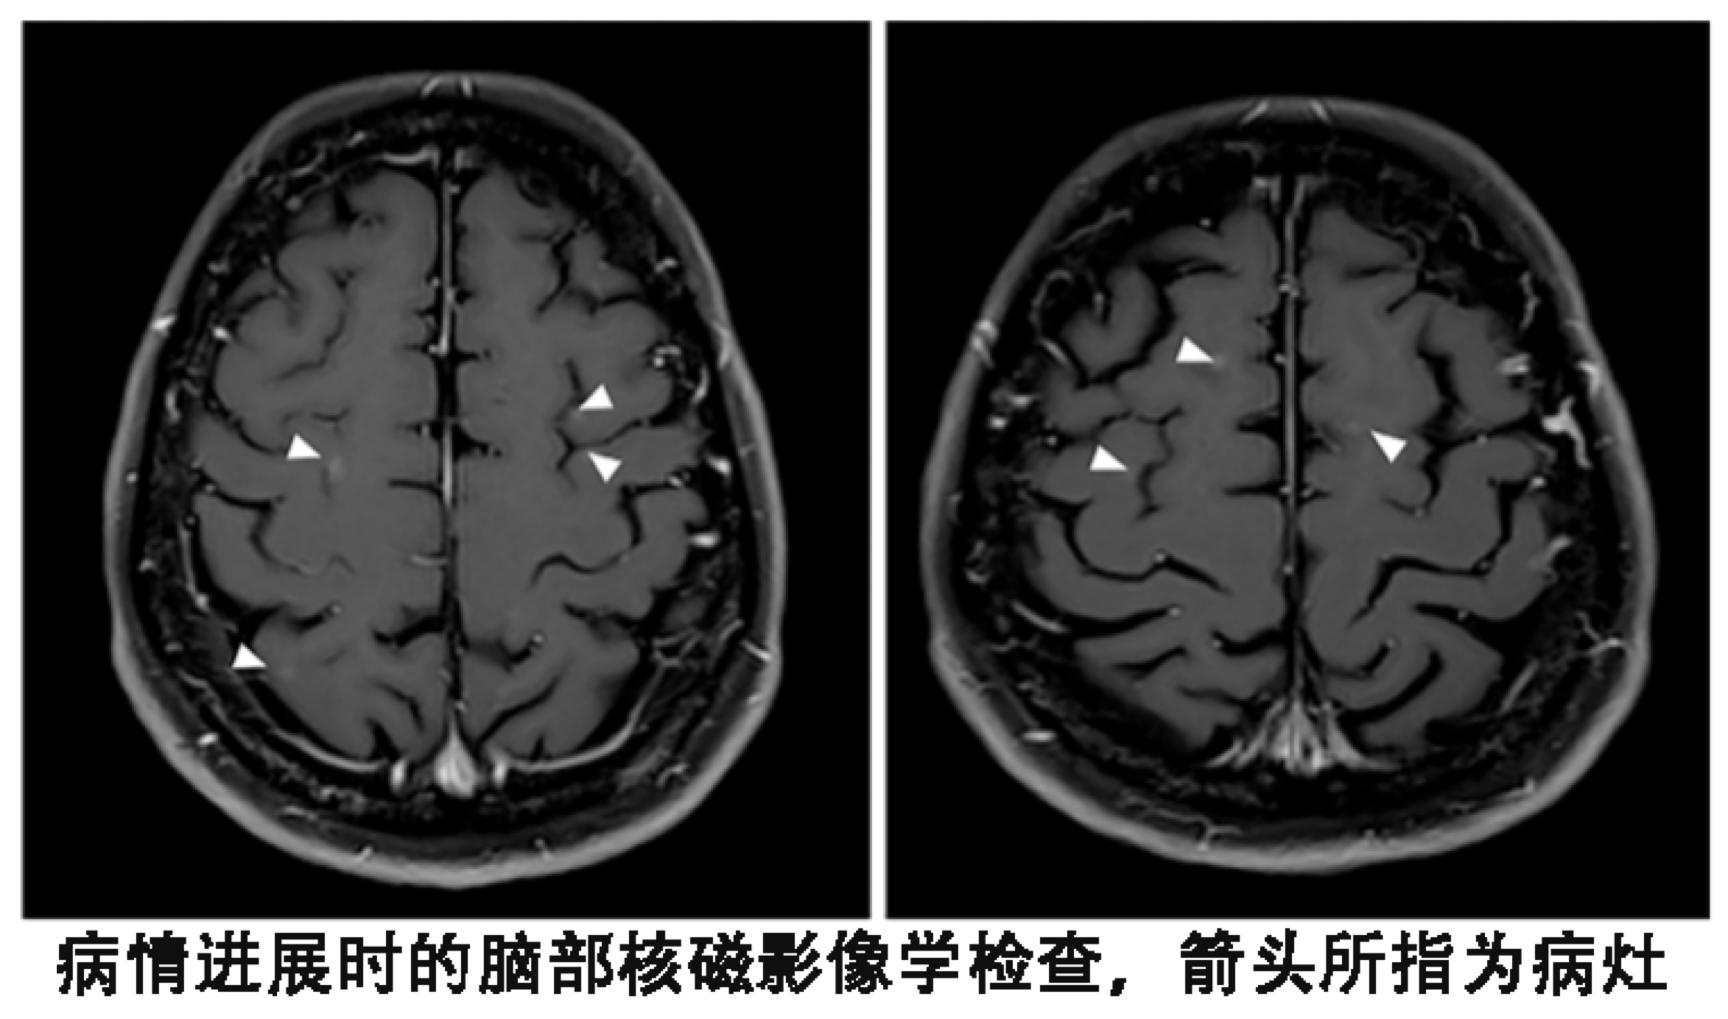

2015年9月,患者进行了视力检查发现双影,根据影像学检查、腰椎穿刺获得脑脊液的细胞学检查,确定脑部病灶进展且出现了脑膜转移。

患者尽管血液基因检测T790M阴性,但是依然换用了第三代靶向药物泰瑞沙(AZD9291),每天的剂量为80毫克,结果出现了奇迹。患者的视觉双影没有了,脑脊液的细胞学检查也为阴性,脑部核磁显示脑皮质损伤有所改善。